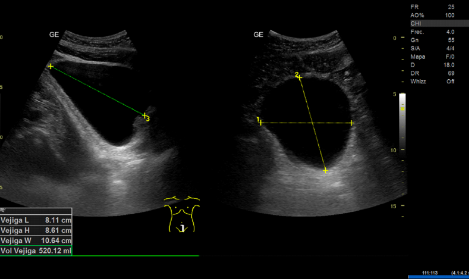

- Ecografía clínica renovesical: Vejiga sin lesiones ocupantes de espacio, sin residuo postmiccional, próstata de tamaño aumentado (56 cc). Ambos riñones con quistes corticales simples, de hasta 9,6 cm en el riñón izquierdo. Sistema excretor derecho no dilatado. Leve-moderada dilatación pielocalicial izquierda. No se evidencian imágenes ecográficas sugestivas de litiasis en pelvis renal.

- Resonancia magnética renal con contraste: hidronefrosis grado II izquierda, secundaria a litiasis obstructiva de 5 mm localizada en el tercio inferior del uréter, inmediatamente caudal al cruce con los vasos ilíacos. Quistes sinusales y simples corticales bilaterales, el mayor de 9,4 cm de eje craneocaudal en el polo inferior del riñón izquierdo. Resto sin alteraciones significativas.